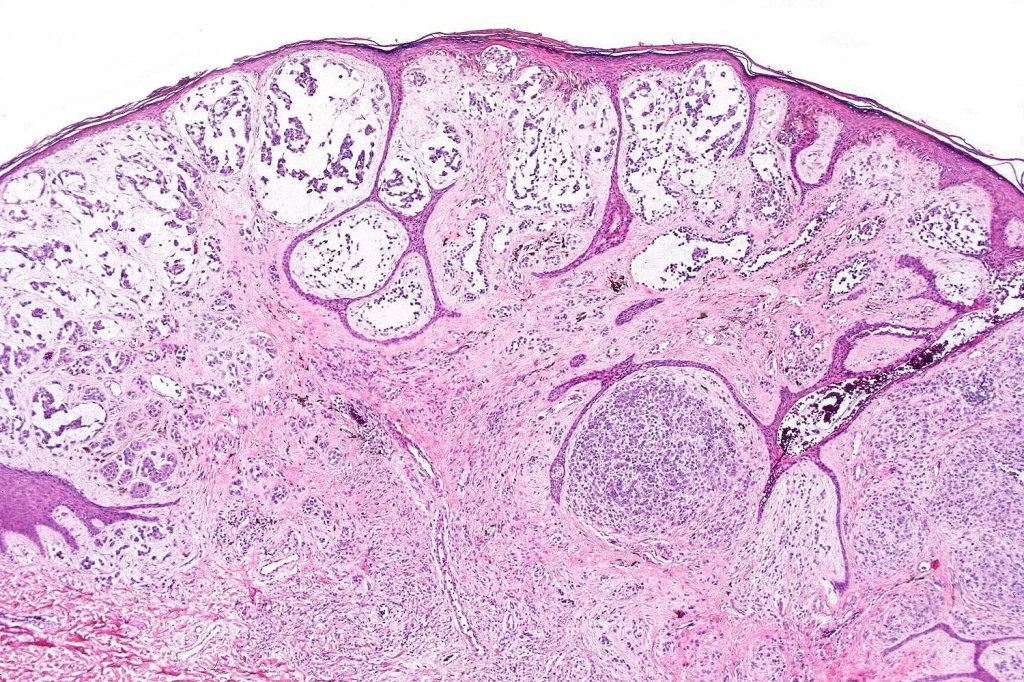

A rare variant of melanoma in which stromal cells produce excess acid mucopolysaccharides inprting a striking myxoid quality. The mucin is Alcian blue & colloidal iron positive, DPAS negative and the melanoma cells stain with typical markeres including S100 & HMB45. It may be seen in primary, recurrent or most often in metastatic lesions. The tumor cells are typically small although occcasionally they are epithelioid. Melanin is often sparse or even avsent making diagnosis difficult. In some examples, a pseudoglandular appearance is seen.

The differential diagnosis is very wide and can include numerous myxoid soft tissue tumors and epthelial mucin-secreting carcinomas. Diagnosis depends on clinical history, mucin stains and the judicious use of immunohistochemistry.